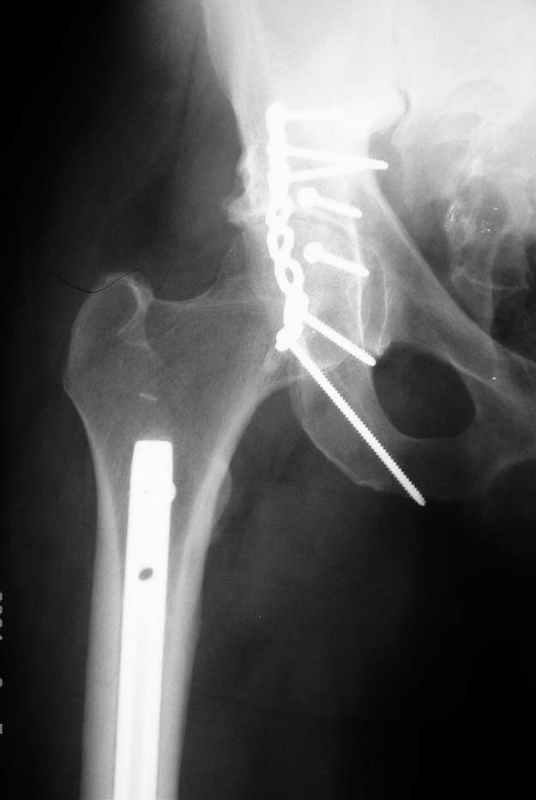

Re: Acetabular fracture

Djoldas kuldjanov, M.D. 02 Сентябрь 2004, 09:05

По снимкам:

Диагноз- перелом с вовлечением таза, разрыв правого сакро-илиак сочленения vertical shear injury, перелом крыла подвздошной кости?, перелом ацетабулум Т type или Both column?, перелом шейки бедра, перелом проксимального отдела бедра.

> Ваш окончательный диагноз?

перелом крыла правой подвздошной кости, перелом обеих колонн вертлужной впадины, двусторонний перелом лонных костей (С2.2) повреждение передних связок правого крестцово-подвздошного сочленения,

ипсилатеральный перелом шейки и диафиза бедра.

К сожалению, набора для ретроградного или антеградного реконструктивного штифтования в операционной нет, поэтому доставка заняла н-ное время. Вопрос, который возник у меня- по поводу оптимальной тактики хирургии: вся фиксация в один этап из расширенного доступа или последовательно сначала бедро и позже реконструкция впадины, комбинированный доступ к впадине отдельно к передней и задней колоннам или из расширенного илеофеморального одного доступа. Все-таки решил остановиться на одноэтапном подходе и спустя 5 дней (как раз и наборы привезли) из расширенного илеофеморального доступа сначала фиксировал реконструктивным штифтом Smith&Nephews бедро и

шейку (благо перелом шейки 2 типа -относительно стабильный) затем фрагмент крыла подвздошной кости Lag screw, далее пластина на заднюю колонну и винты в переднюю колонну.(с размерами и направлением винтов ошибка вышла:-((, но интраоперационно у меня была полная уверенность , что винты *ушли* в лонную кость).

Еще раз спасибо за комментарии и готовность помочь с имплантами. Постоп картинки в приложении,